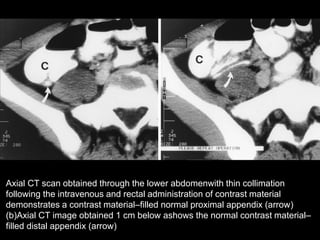

Axial CT scan obtained through the lower abdomenwith thin collimation

following the intravenous and rectal administration of contrast material

demonstrates a contrast material–filled normal proximal appendix (arrow)

(b)Axial CT image obtained 1 cm below ashows the normal contrast material–

filled distal appendix (arrow)